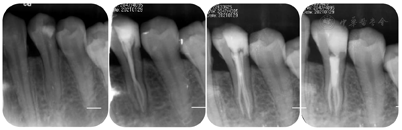

34远中邻牙合面可见白色暂封材料,部分脱落松动,叩痛(±),不松动,牙龈龈缘稍红肿,无窦道口,牙髓活力测试:无反应,咬合:无异常动度。见图1。根尖片示:34牙冠远中邻合面高密度充填影像达髓腔;髓腔高大,髓室底低,根分叉向根方移位,牙根中下1/3膨大,根管影像不清,根周膜影像不清。见图2A。CBCT示:⑴横断面:髓腔高大,髓室底低,牙根下段根管形态复杂,中下1/3牙根横截面呈C形(见图3A、3B);⑵近远中观:颊侧通路影像清晰,舌侧通路影像不清,髓室底距颊尖约:14.0mm,髓室底距CEJ约:7.6mm(见图3C、3D),测量牛牙症指数(taurodontic index,TI),AB:15mm、AC:7.6mm,AB / AC x100%= 50.7%,为重度牛牙症(见图5);⑶颊舌侧观:舌侧通路弯曲明显,呈"S"形,根尖1/3根管影像不清(见图3E)。

治疗过程:34去除暂封材料及棉球,洞壁见大量腐质,颊侧及舌侧的髓室顶未完全揭除(见图7A);去净腐质,玻璃离子制作假壁,上橡皮障,揭净髓室顶,显微镜下见髓腔狭窄,髓室底深。依据术前CBCT测量数据:髓室底距颊尖:14.0mm,髓室底距釉质牙本质界CEJ:6.5mm,在显微镜下,使用超声ET20去除牙本质领,修整、扩大髓室壁,建立直线通路。见髓室底有钙化物,同时去除髓室底钙化物,充分暴露髓室底,DG16仅探及颊侧通路,C+疏通,扩大至15#。在CBCT上对远舌通路进行定位,远舌通路位于颊侧通路远中舌侧约2.0mm(见图3F),显微镜下,ET25逐层去除根管口牙本质领,充分暴露远舌通路根管口,根管弯曲细小,伴有弥漫性钙化,依次使用6#、8#、10# C锉,尖端2mm预弯,结合EDTA凝胶逐号疏通根管,1%NaClO大量冲洗,回挫,电测根管长度:B=21.0mm,DL=19.0mm,镍钛预备根管,B:25# 6%,DL:25# 4%。试主尖,根尖片发现根管有遗漏(见图2B)。再次结合CBCT对近舌通路进行定位CBCT颊舌观:近舌牙根弯曲,根管影像不清(见图6B);横断面:近舌通路根管口位于颊侧通路远中舌侧1.5mm,远舌通路近中颊侧约1.0mm,近舌通路根管口牙本质领较厚(见图6A),显微镜下,ET25少量缓慢逐层去除1~2mm钙化物及牙本质领,小号锉反复探查,探及近舌通路根管口;疏通方法同远舌通路,电测根管长度:ML=19.0mm,EDDY尖结合1%NaClO声波活化荡洗,试主尖,X线片示:到达工作长度(见图2C),根管内封入Ca (OH )2糊剂,玻璃离子暂封。2周后复诊,患牙未诉不适,iRoot sp单尖充填3通路,髓腔热牙胶回填,完成根管治疗。术后拍摄X线片显示,根管充填恰填(见图2D)。